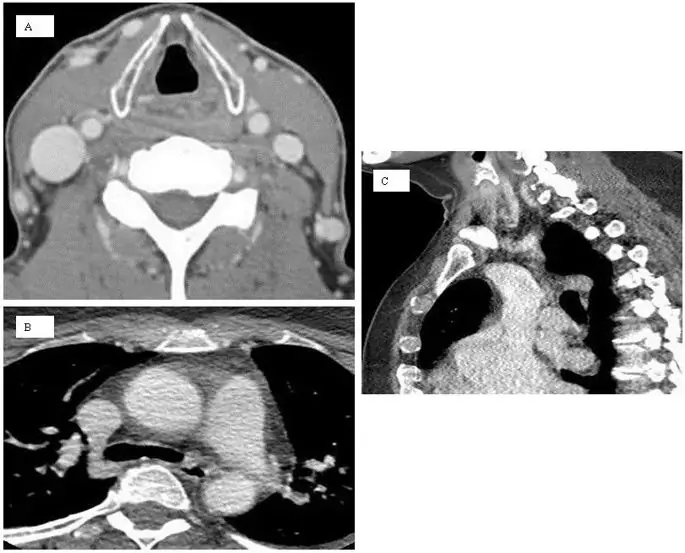

figure7

Пример компьютерной томографии венография внутренних яремных и азигозных вен. Аксиальные (А) реконструкции внутренних яремных вен. Показаны осевые и сагиттальные реконструкции азигозной вены и С), но их диагностическая ценность сомнительна.